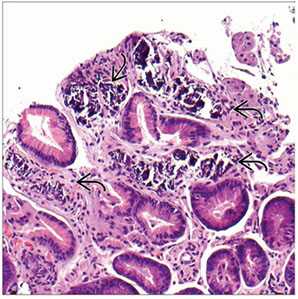

Figure 1: Gastric mucosal biopsies from children with autoimmune enteropathy often showed features of (a) chronic gastritis with increased lamina propria lymphoplasmacytic inflammation forming a superficial band within the mucous neck region. (b) In some cases, prominent intraepithelial lymphocytosis was identified within the surface, foveolar epithelium consistent with lymphocytic gastritis. (c) Concurrent autoimmune-related disorders were a common finding in patients with autoimmune enteropathy. Gastric biopsies taken from the fundus of case 14 demonstrated the features of autoimmune atrophic gastritis with partial parietal cell loss and superficial intestinal metaplasia. (d) In a subset of patients, multiple apoptotic bodies (arrows) were identified within the deep glandular mucosa.